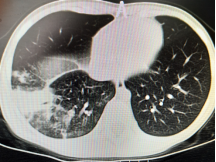

在常见病多发病诊疗基础上,对呼吸系统疑难危重者的诊疗也有独到的优势:重症肺炎的介入治疗(包括盥洗;介入手术取塑性支气管束挽救几近闭塞气管获得再通;利用电切球囊扩张二氧化碳冷冻技术挽救坏死陷闭的气管支气管),支气管异物的取出(包括超过4周的异物造成局部肉芽组织增生、桥联等的诊疗),肺不张的介入治疗可挽救不张的肺叶,降低肺叶切除的风险。支气管扩张症患者定期气道盥洗可改善支扩患儿的生活质量及缺氧情况。已开展气管镜内膜刷检及活检,对EBTB(支气管内膜结核)的诊断,后期可进行局部治疗(包括局部予以异烟肼滴注、钳夹干酪病灶促进病灶恢复等)。随着呼吸专业科研水平提高,对于哮喘支气管哮喘诊断及治疗获得满意的临床疗效,根据炎症介质、哮喘易感基因、哮喘个体化给药基因检测指导临床精准用药、肺功能评估一系列方法的选择,提高了哮喘的诊疗水平。随着二代测序(全外显)的开展,呼吸系统单基因遗传病(囊性纤维化、PCD等)的诊断率逐渐提高,同时呼吸系统病原学的宏基因检测越来越多的应用于临床,减少及避免的抗生素的不合理应用,做到精准诊断精准治疗。

以下为呼吸专业典型病例分享:

图片2:气管狭窄后电切、球囊扩张、二氧化碳冷冻治疗